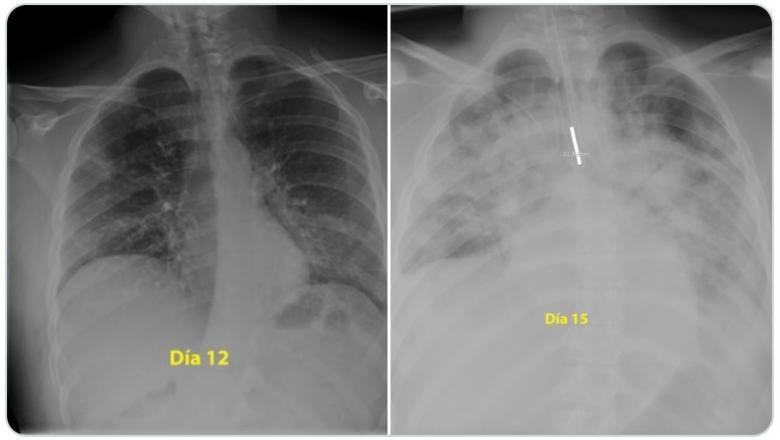

În doar trei zile, plămânii bărbatului au fost măcinați de penumonie, lucru pe care medicul îl explică în imaginile atașate.

Prima radiografie a fost realizată în a 12-a zi de boală a tânărului, a doua în a 15-a zi de boală, după cum sugerează și imaginile.